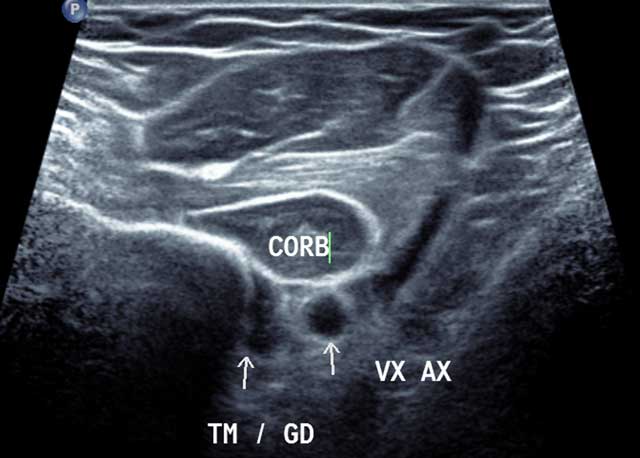

Axial distal section of humeral insertion in external rotation of the thick portion of the Coracobrachialis, of the brachial artery below the sub scapularis and the Pectoralis Major. The myotendinous junction of the brachial biceps only needs to be located behind the insertion of the Pectoralis Major and the probe shift to the medial arm (Figure 4).

Figure 4

Axial distal section of the anterior and medial humerus area in external rotation. CORB: Coraco Brachal Muscle, TM/GD: Common enthesis of Teres major and Latissimus Dorsi, VX AX: Axillar Artery.

As in Teres Major, the humeral insertion is ultrasound-guided through an anterior approach and the arm in external rotation (Figure 4). Yet the myotendinous junction is explored through an axillary posterior approach, the arm in internal rotation.